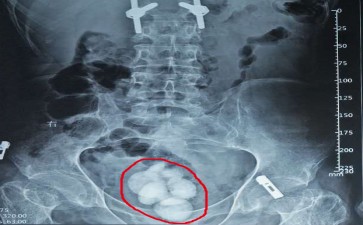

你是否经历过这样的尴尬时刻:明明尿意汹涌,却只能断断续续挤出几滴;或是排尿时突然一阵剧痛,仿佛有根针在膀胱里乱戳?这些让人苦不堪言的症状,很可能就是膀胱里的“小石子”——长春结石医院膀胱结石在作祟。

这些“小石子”一旦形成,就会在膀胱里“横冲直撞”。它们刺激膀胱黏膜,引发尿频、尿急、尿痛,严重时还会导致血尿。更糟糕的是,较大的结石还可能堵塞膀胱出口,让你排尿时突然“卡壳”,痛苦不堪。